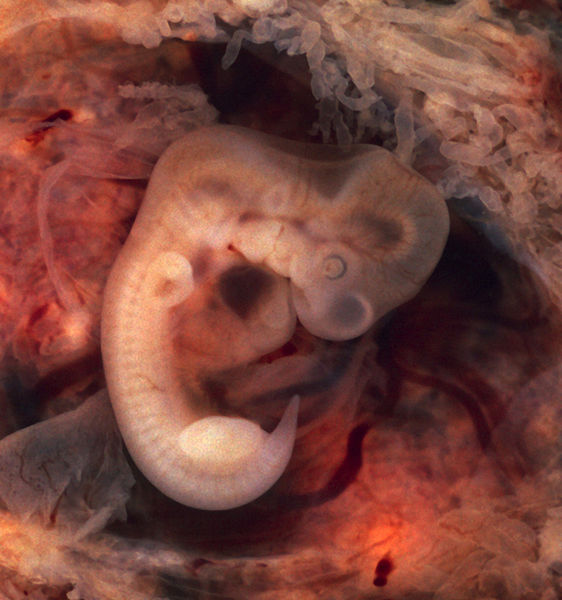

English: Human Embryo (7th week of pregnancy, 5th week p.o.)

This photo of an opened oviduct with an ectopic pregnancy features a spectacularly well preserved 10-millimeter embryo. It is uncommon to see any embryo at all in an ectopic, and for one to be this well preserved (and undisturbed by the prosector's knife) is quite unusual.

Even an embryo this tiny shows very distinct anatomic features, including tail, limb buds, heart (which actually protrudes from the chest), eye cups, cornea/lens, brain, and prominent segmentation into somites. The gestational sac is surrounded by myriad chorionic villi resembling elongated party balloons. This embryo is about five weeks old (or seven weeks in the biologically misleading but eminently practical dating system used in obstetrics).

The photo was taken on Kodak Elite 200 slide film, with a Minolta X-370 camera and 100mm f/4 Rokkor bellows lens at near-full extension. The formalin-fixed specimen was immersed in tap-water and pinned to a tray lined with black velvet. The exposure was 1/4 second at f/8.